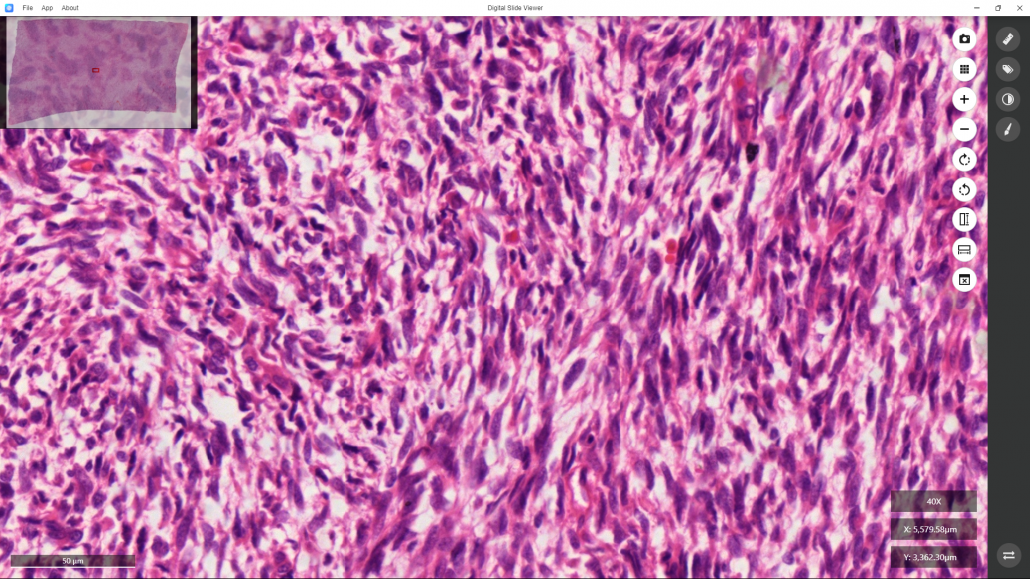

In contrast, turning the mouse scroll wheel backward or clicking the “-” command at the right bar of the software will shrink the image. Here the enlarged image is shown:

A small window at the top left corner shows the location of the enlarged image in the entire section.At this highest magnification, indicated by “40X” (objective lens) shown at the bottom right corner.